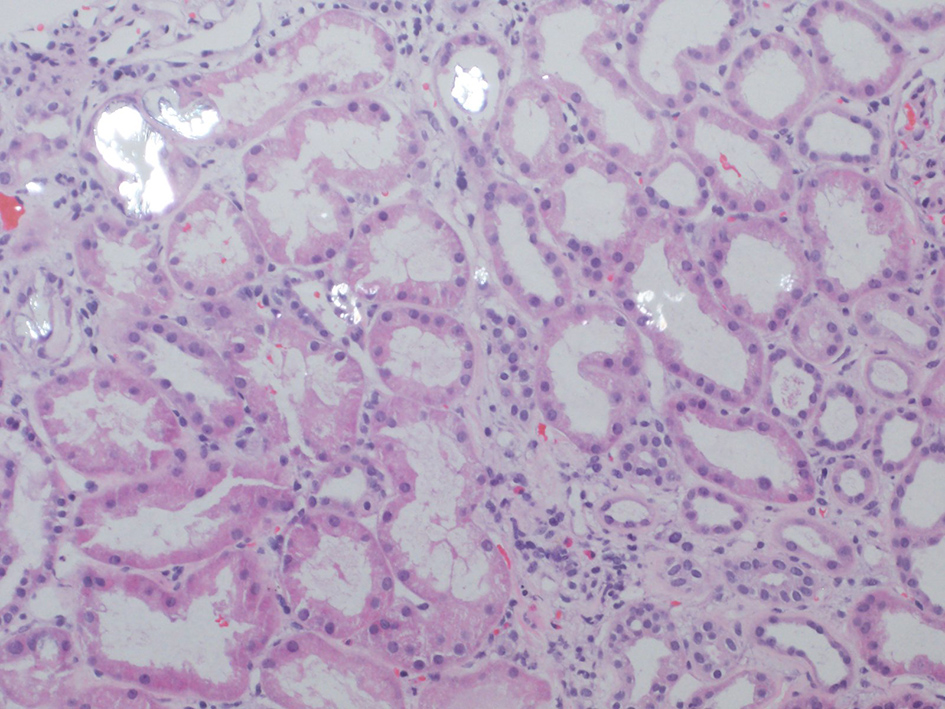

After several days of care and an unremarkable renal ultrasound, a renal biopsy was ordered. The pathology demonstrated 13 out of 23 glomeruli to be globally sclerotic, as well as areas of capillary loop wrinkling and periglomerular fibrosis (Fig. 1). Patchy areas of acute tubular injury were present, with moderate numbers of injured tubules containing luminal calcium oxalate crystals, consistent with oxalate nephropathy (Figs. 2 and 3). Additionally, there was severe interstitial fibrosis and tubular atrophy involving an estimated 60% of the submitted parenchyma, and moderate fibrointimal thickening of small arteries and severe hyalinosis of arterioles (Fig. 4). Immunofluorescence staining for IgG, IgM, IgA, C3, C1q, albumin and fibrinogen were negative, and kappa and lambda light chains stained equally throughout the tubulointerstitium.

![]() Click for large image | Figure 3. Injured tubules with luminal oxalate crystals. |